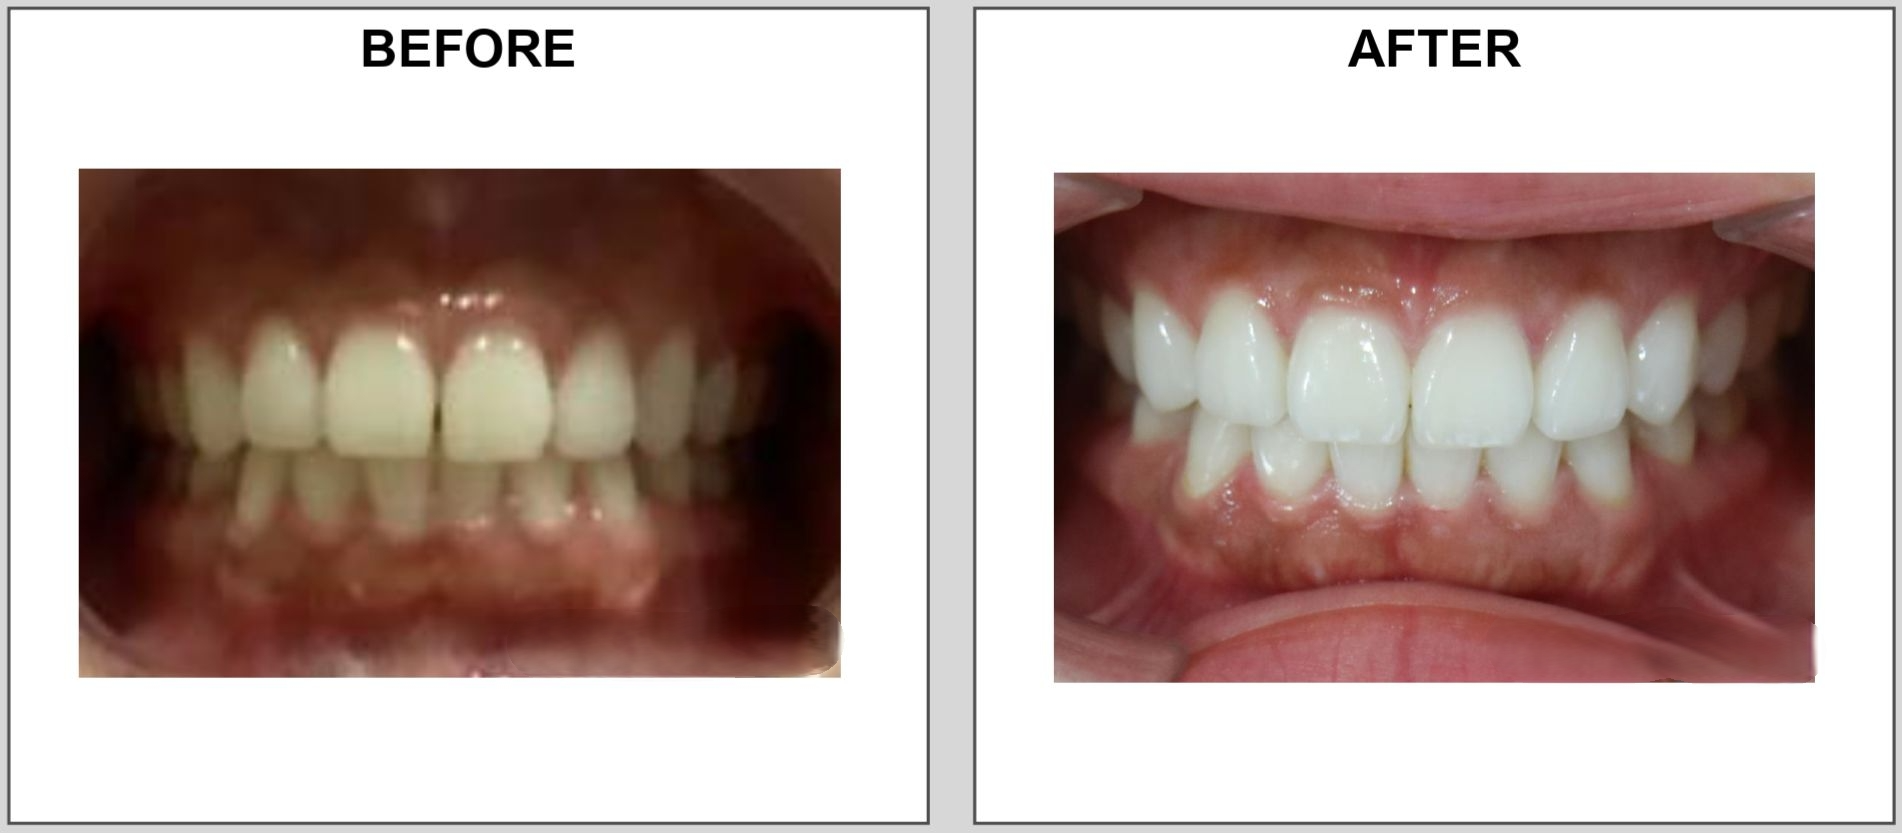

| 【主訴】 | ・上の前歯の隙間 |

| 【年齢・性別】 | ・20代・女性 |

| 【診断名】 | ・空隙 |

| 【治療内容】 | ・マウスピース矯正aaligner |

| 【ステージ数】 | ・3ステージシミュレーション ・3ステージで終了 |

| 【実際の治療期間】 | ・3ヵ月程度 |

| 【通院回数】 | ・2回(初回セット時含む) |

| 【費用】 | ・198,000円 +IPR処置料3,500円×1回 |

| 【リスク】 | ・マウスピースの装着不良や着用時間(1日20〜22時間以上)の未達により歯が動かない ・一時的な咬合痛や疼痛 ・三角空隙、歯根吸収、歯肉退縮の発生 |